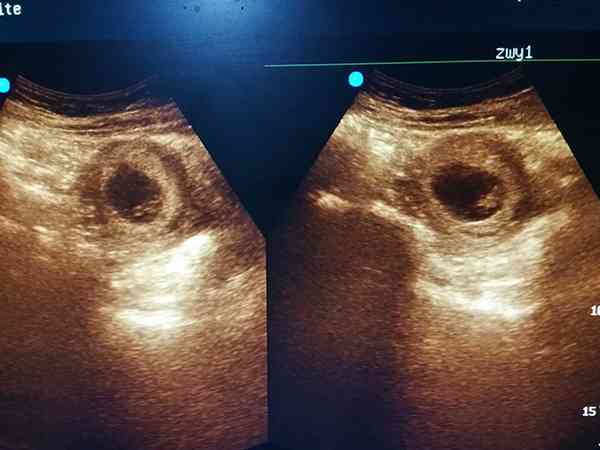

懷孕42天去私人醫院做的四維,四維機器上看到的孕囊圓圓的,醫生說是丫頭,如果是長長的就是小子,我這都第三胎了,前面兩個女寶,聽他這樣子說傷心死了,但我有個閨蜜當時孕囊就是圓的,很多人都說是女孩,結果生了個男孩。所以我還是抱有一絲絲希望,想問問大家早期孕囊圓生男孩的多嗎?早期孕囊圓生男孩的也多,但是生男孩與孕囊圓不圓無關,也就是說與孕囊形狀、大小都是沒有任何關係的,只與性染色體有關。當男性的Y精子與卵子結合受精那就是男孩,男性的X精子與卵子結合受精那就是女孩。做四維是可以看出胎兒性別的,但是在我國是禁止的。而且你才懷孕42天,一般胎兒的性器官在12周的時候才開始發育。

一般來說,XY染色體的妊娠囊,是長條形的;XX染色體的妊娠囊,形狀相對比較圓,網上已生男孩孕囊圖片可以看出孕囊的形狀像茄子,或者是呈長條狀的,則懷上男寶寶的可能性大;而如果孕囊是橢圓形或圓形的,那麼很可能就是個女寶寶了。還有以下4點判斷生男生女: